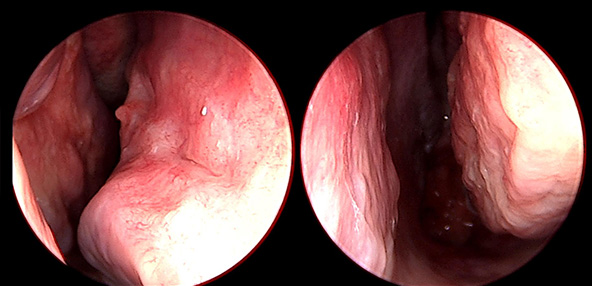

※ 비중격 비염 수술 후 생길 수 있는 부작용으로는 출혈, 감염, 염증이 있을 수 있습니다.

본 사진은 의료기관에서 진료를 본 환자이고, 전후 사진 인물이 동일인이며,동일조건에서 촬영이 되었습니다.